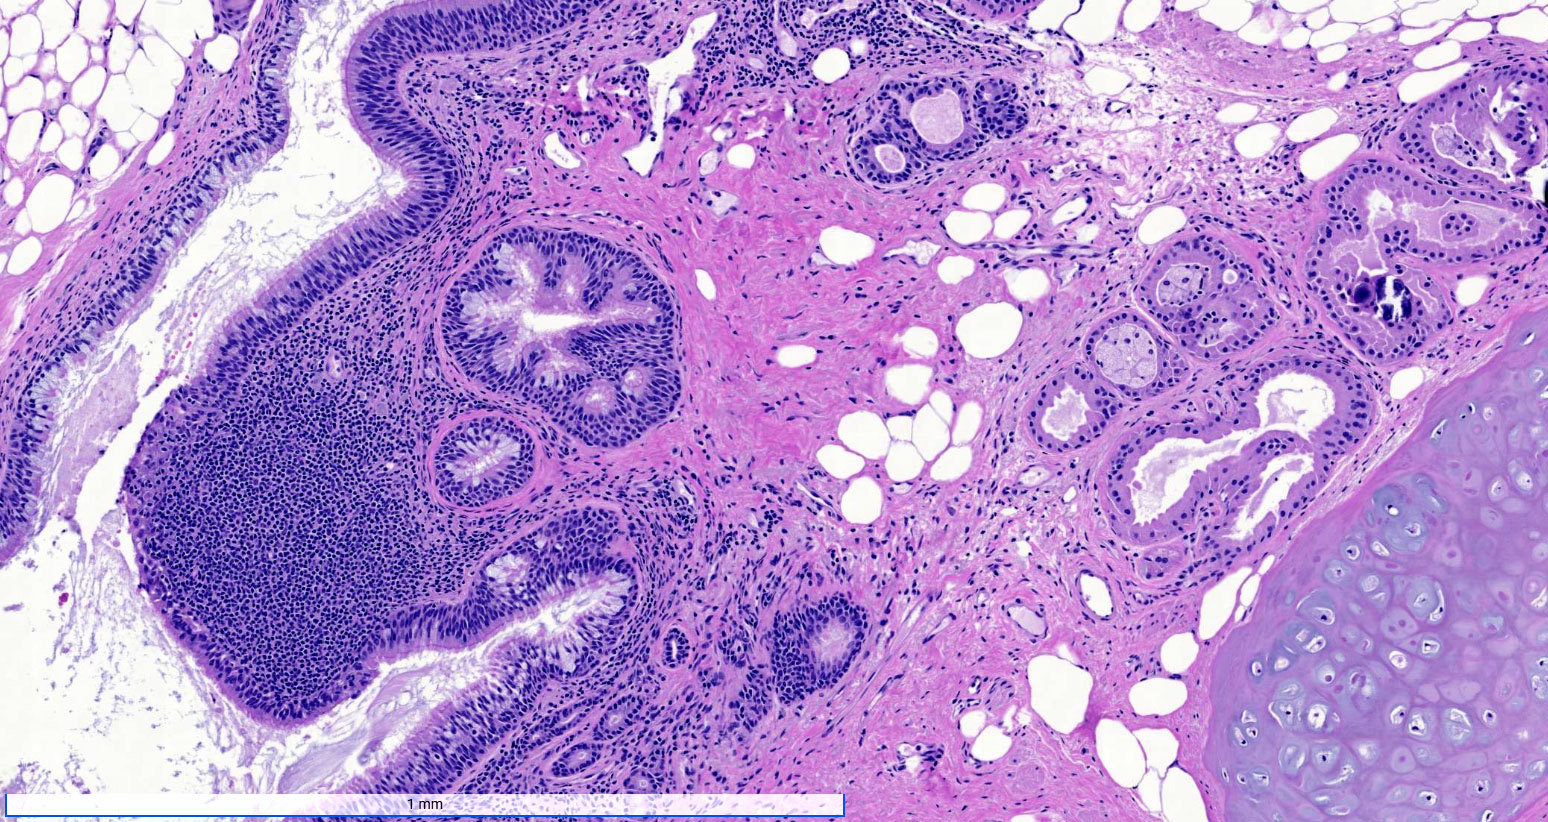

Microscopic (histologic) description

- Mixture of mature, benign tissues

- Ectodermal (most common): squamous epithelium, sebaceous glands, hair follicles, brain tissue

- Mesodermal (second most common): bone, cartilage, smooth muscle, fibroadipose tissue

- Endodermal: intestinal or respiratory epithelium, thyroid, salivary gland

- Microscopic foci of immature neuroepithelium (less than or equal to 4 foci or 21 mm2) does not warrant diagnosis of immature teratoma and will not affect prognosis (Int J Gynecol Pathol 1987;6:203)

- Fat necrosis and foreign body reaction may be seen

- Cases associated with NMDAR encephalitis usually show neuroglial tissue associated with lymphoid aggregates with germinal centers, low number of mature neurons and a hypercellular astrocyte population (Am J Surg Pathol 2019;43:949)

Microscopic (histologic) images